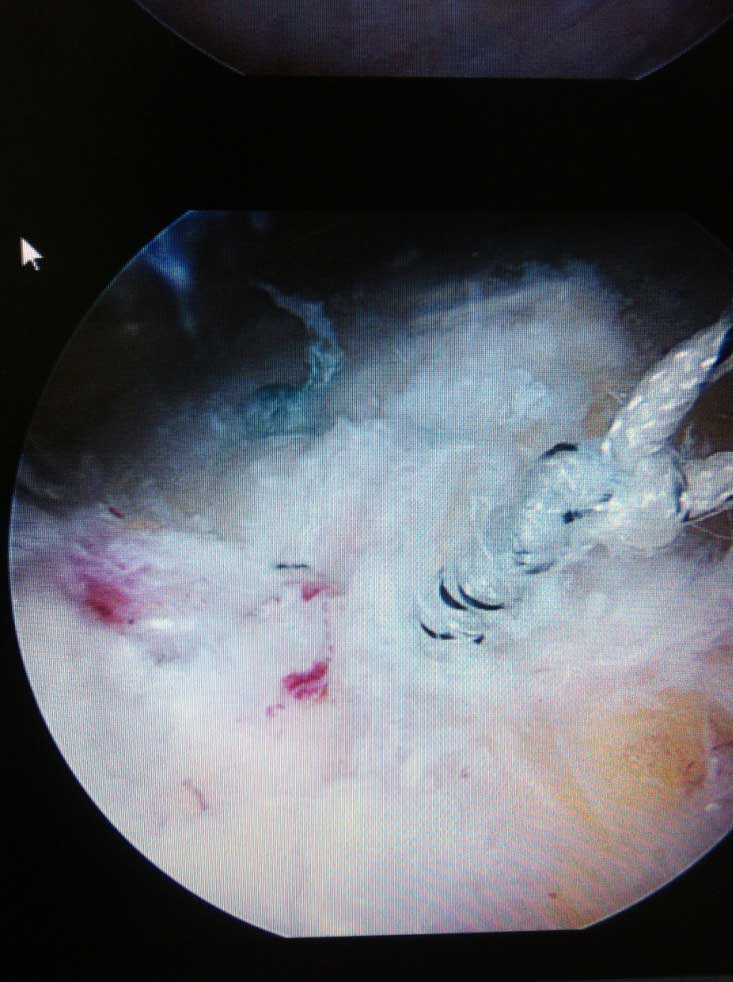

Je nach Alter, Verletzungsmuster, Anzahl der Luxationsereingnisse und weiteren Faktoren, wird eine schulterstabilisierende Operation indiziert und empfohlen. Diese führen wir ebenfalls ausschliesslich arthroskopisch

(Schüsselloch Operation) durch. Innerhalb von 15 - 30 min wird dabei der knorpelige Ring (s.g. Labrum) auf den knöchernen Pfannenrand mit speziellen Anker und Fäden wieder zurück befestigt.

Die Nachbehandlung richtet sich nach Schwergrad der operativ versorgten Verletzungen, beträgt allerdings in d.R. nicht länger als 8-10 Wochen, inkl. Rückkehr zu Kontaktsportarten binnen 12 Wochen nach Operation.